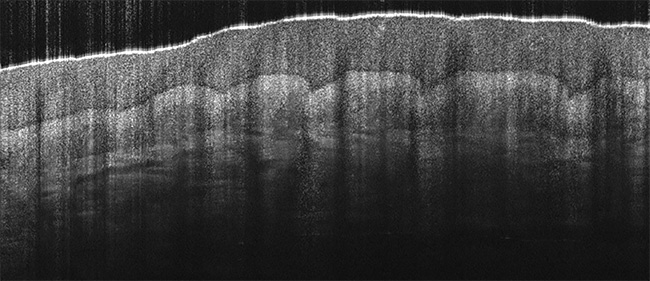

OCT has gained popularity as an imaging modality due to its ability to provide images with much higher resolution than ultrasound, without the need for direct contact with a specimen or use of a coupling medium. While it was introduced into the mainstream as an ophthalmology technique (Figure 1), OCT is now viewed as a more broadly applicable approach to noninvasive biomedical imaging. It provides surface profiles and information about subsurface structure and uniformity up to a few millimeters in depth, with applications in medical fields such as ophthalmology, dermatology (Figure 2), cardiology, and life sciences research. It also has uses outside the life sciences and medicine, in industrial inspection, and even for the analysis of art and historical artifacts.

Figure 2. 800-nm spectral-domain optical coherence tomography (SD-OCT) image of a finger, showing the epidermis and dermis layers. Courtesy of Wasatch Photonics.